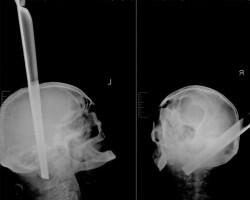

Фото Пробитых Голов

Фото Пробитых Голов 110 фото